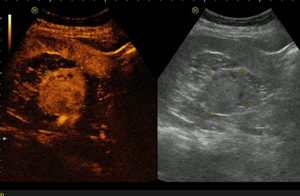

Ультразвуковое исследование почек и мочевого пузыря

- Исследование в В-режиме конвексным датчиком

- Исследование в режиме ЦДК и ЭДК

- Контрастно-усиленное УЗИ (КУУЗИ)